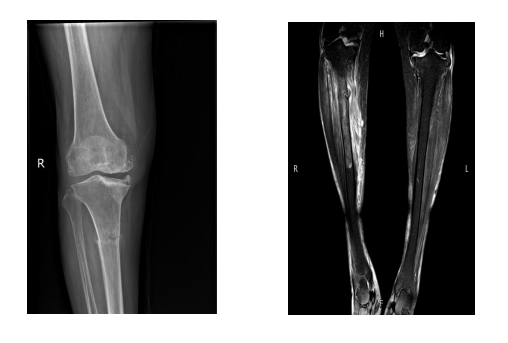

6月前,62岁的胡阿姨因为反复右小腿肿胀、疼痛5天就诊于我院,经方伟医师细致检查后诊断为“右胫骨骨髓炎伴胫骨病理性骨折”,同时合并有膝关节骨关节炎、骨质疏松症等多种疾病。病初予以止痛消肿抗感染、石膏制动等保守治疗未见明显好转。

为什么负压引流【前沿技术】负压封闭引流联合Masquelet技术治疗“不死癌症”——骨髓炎_https://www.jmylbn.com_新闻资讯_第4张